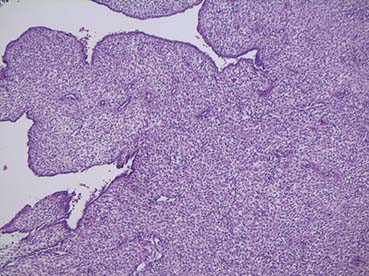

Decidual cast

Een 45-jarige vrouw komt op het spreekuur met een stuk weefsel dat ze die ochtend vaginaal heeft verloren. De nacht ervoor had ze veel buikpijn en vaginaal bloedverlies gehad. Er zijn geen tekenen van een zwangerschap. Ze was een half jaar daarvoor op het spreekuur geweest in…